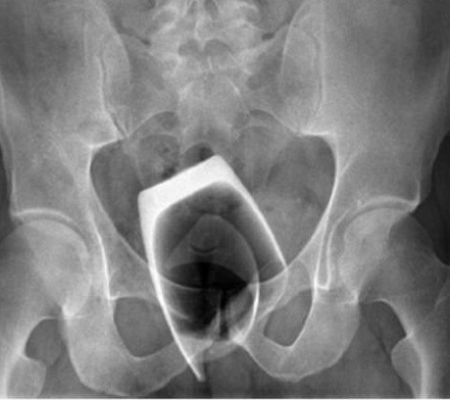

Nos exames de raio-x os médicos puderam confirmar a história do italiano. Era possível ver o contorno do copo nitidamente “travado” na região do reto, com o lado inferior voltado para cima, conforme afirmaram os profissionais ao BMJ Case Reports. Ao perceber a gravidade do caso, o homem foi imediatamente transferido para a ala de operações, com pedido de urgência para a realização de cirurgia. O procedimento consistiu em dilatar o reto do paciente para ampliar a passagem de um dispositivo para examinar o local. Com esse instrumento, os fragmentos mais afiados conseguiram ser extraídos, e o restante foi expulso do corpo usando fórceps.